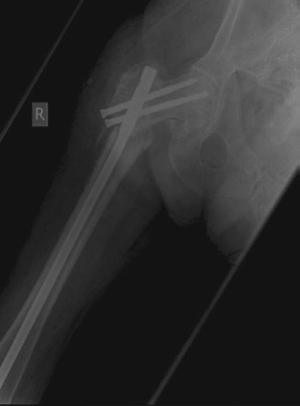

CANDIDATE : This is an AP radiograph of the right hip showing a reverse-obliquity inter-trochanteric fracture with subtrochanteric extension. The lesser trochanter is proximally displaced with loss of the medial buttress. I would like to see a lateral radiograph, however, based on just the AP view, it is an unstable fracture pattern.

Figure 8.9 Anteroposterior (AP) radiograph right femur demonstrating inter-trochanteric fracture.